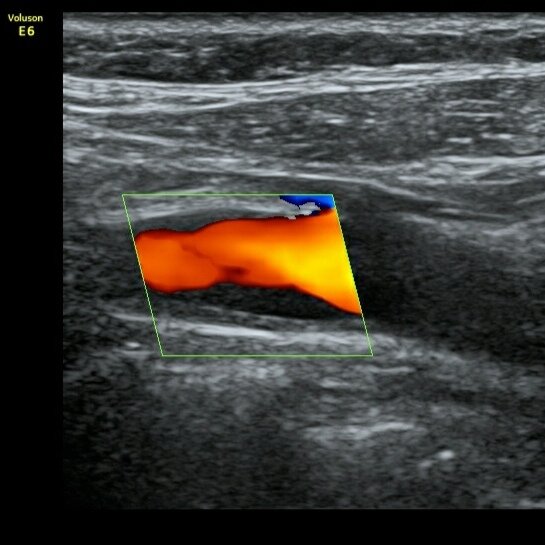

Бляшка с покрышкой

🖼️Типичная картина "Бляшка с покрышкой". Внутри бляшки происходит кровоизлияние, в итоге эхогенность соответствует просвету артерии. При этом видна наружная яркая часть - капсула, она же "покрышка".

👨‍💻Такая находка - бомба 💣 с часовым механизмом. При повреждении покрышки развивается тромбоз и эмболия в артерии мозга. Как итог - инсульт.